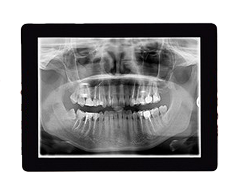

Digital X-Rays

Digital X-rays are one of the most important tools we use to protect and care for your child’s smile. They give us highly detailed images of teeth, gums, and jaw growth—helping us spot issues that may not be visible during a regular exam.

The benefits of our digital X-ray system include:

- Lower Radiation Exposure – Up to 90% less radiation than traditional film X-rays.

- Instant Results – Images appear on-screen within seconds, making it easier to explain findings and next steps to parents.

- Greater Comfort – Smaller, child-friendly sensors mean a quicker, more comfortable process for kids.

- Eco-Friendly – No chemicals or film processing, making it a safer choice for both patients and the environment.

Our gentle, kid-focused approach means we take the time to explain the process in age-appropriate terms, helping children feel relaxed and involved in their own care.